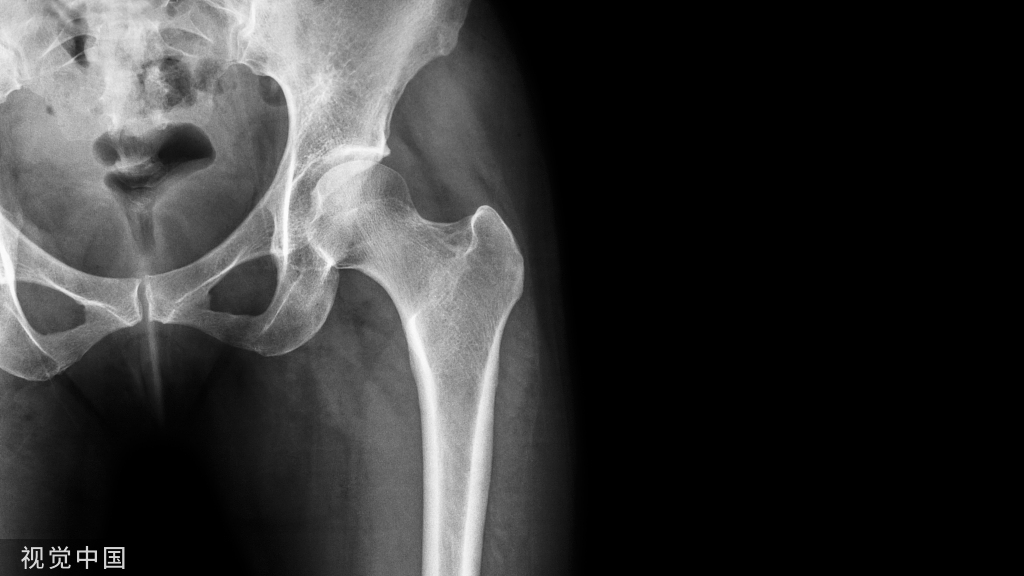

髋关节的X线解剖

常规拍摄正位(见图1)和侧位X线片。正位线片上,因髋臼三骨之间以“Y”形软骨相连,融合之前,表现为横行带状透亮影,其宽窄随着年龄变化而改变。年龄越小此透亮带越宽;年龄越大,透亮带变窄,15~17岁左右消失。股骨头大部套在髋臼内,表面光滑,为致密的细弧线。头的中心偏后下部有一小凹陷,是股骨头凹,有时可投影到股骨头弧线内侧,显示为小环形透亮圈。侧位片上,中央的凹窝是髋臼,呈半圆形的致密线。